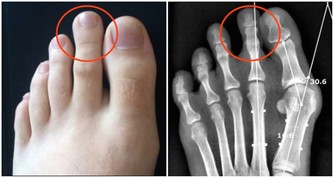

愛放屁且淨放臭屁很可能是患上了足以致命的疾病—大腸憩室炎,尤其是對於長期便秘的人群來說,尤其要注意,便秘的人每次排便都要對腸子施以很大壓力,時間長了,憩室就可能被一個一個擠出來,所以要注意緩解便秘,經常便秘者要趕緊治療,不可小視。平時要多吃一些潤腸排便的纖維含量高的食物, 或者按摩腹部, 飯後半小時適當運動, 加強胃腸蠕動,也有助於改善便秘。